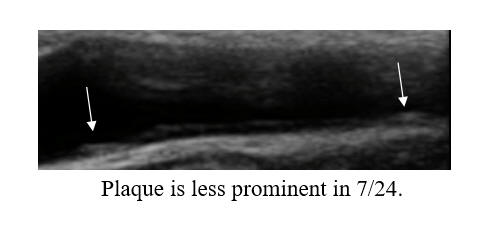

I began working with PM in '07, 14 years ago. Chest tightness, then associated with a non-threatening stress test, resolved following 20 IV EDTA treatments. PM's IMT of 0.678 was below-average-for-age; carotid plaque was not identified. PM began a program of risk factor reduction, but we could not dent PM's LDL elevation (150-180 mg/dl), at least not with treatments that PM could tolerate. PM's IMT rose between '08 and '22, at an average rate of 0.007 mm per year, but calcific carotid bulb plaque had developed over this interval. PM received two months of cyclodextrin in '23, as a proactive preventative, our theory being that if we can't lower PM's circulating lipids, perhaps we could make up by pulling lipids out of the vascular wall. PM's IMT was repeated in 1/25, and demonstrated active IMT regression, at a rate of 0.02 mm per year (a lot). Thus PM's predisposition towards plaque formation was reversing, and of greater importance to PM, we observed plaque regression. The right carotid bulb plaque, which had developed over 14 years, decreased in size over two years! Our plan, going forward, will be for PM to complete two moths of cyclodextrin every year, with a repeat carotid study in 2-3 years.